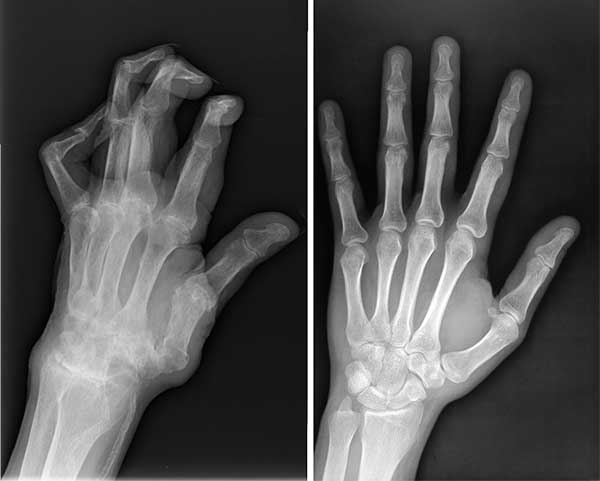

Saya bukan satu-satunya yang diselamatkan oleh produk ajaib ini. Suami saya menderita sakit di lengannya untuk waktu yang lama. Jari-jarinya mengalami cedera parah, dan kemudian didiagnosis menderita radang sendi. Saya memutuskan membeli Rosel's untuk dia. Kami minum bubuk ini bersama-sama dan produknya berhasil menyembuhkan kita berdua.

Rontgen suami sebelum dan sesudah mengonsumsi Rosel's

Keadaan tangan suami saya sebelum dan sesudah mengonsumsi Rosel's